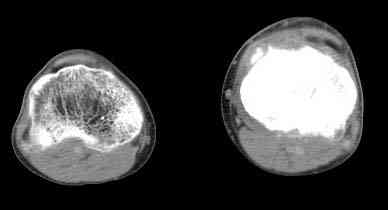

важаемые коллеги! Поступил больной 22 лет. Болен с января 2006 - появились боли в области верхнейтрети голени. При первичном осмотре в поликлинике был заподозрен первично-хронический остеомиелит - осмотрен гнойным хирургом - произведена биосия . Заключение - хондросаркома. Осмотрен онкологом - с учетом характера опухоли - химиотерапия, лучевое лечение не показано. Предложена либо ампутация, либо решение вопроса о возможности выполнения органосохраняющей операции. При обращении к нам произведена сцинтиграфия скелета - зоны гиперфиксации РФП: верхняя треть голени- 960%, нижняя треть бедра - 380%, Дистальный метафиз голени и затылочная область - 140%. В легких - метастазов нет. Произведена КТ (картинки в приложении). Учитывая абсолютную нестыковку рентгенологических и морфологических данных повторно биопсия. Выявлено, что первичная биопсия выполнялась из поверхностной параоссальной зоны - там локализованы хрящеподобные массы, далее очень плотная кость без хрящевых участков - биоптат взят фрезой с большим трудом. Морфологического заключения пока нет. Хотелось бы узнать Ваши варианты диагноза и соответственно тактику.

Не специалист по онко ортопедии, но по локализации (бедро, большеберцовая и плечевая кость), возрасть, в данный момент отсутствия метастаза и формация новой кости с мягкотканним вовлеченим, процесс больше напоминает остеосаркому большеберцовой кости.